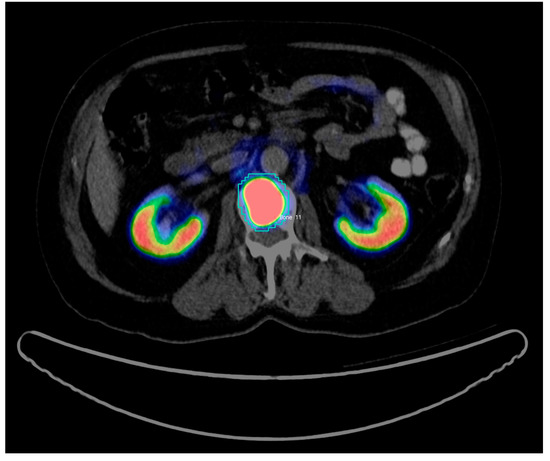

For each scan, all the hotspots have been identified and manually delineated consecutively by two trained nuclear medicine (NM) physicians (both board-certified and with 7 and 3 years’ experience in PET/CT) using InterView FUSION software V3.08.005 (Mediso Medical Imaging Systems, Budapest, Hungary [18]) (see Figure 1). Hotspots were defined as focal uptake beyond the local background without any specific threshold. To define each 3D hotspot, all its 2D counterparts were delineated in subsequent slices. Hence, the hotspots were analyzed as fully connected 3D volumes. The hotspots included malignant tissues in any organs and metastatic uptakes in bones or lymph nodes as well as physiological uptakes in kidneys, livers, etc., as well as benign or unspecific uptake, e.g., in the thyroid. Per hotspot, a total of 80 (40 PET-based+40 CT-based) features were calculated by InterView FUSION software (the standard set of radiomics features provided by the software). The features include first and higher order statistics features (mean, max, kurtosis, etc.), shape-based features (max diameter and volume), textural features (entropy, contrast, homogeneity, etc.), and volumetric zone and run length statistics (grey-level non-uniformity, short run emphasis, etc.). See Table 1 for a detailed list of the radiomics features. Afterwards, the ground truth labels were merged with the features calculated by InterView software using our internal PET/CT scan annotator software (Python V2.7).

Figure 1. Example of Region of interest (RoI) definition for a bone PET/CT hotspot in InterView FUSION Software. The 2D slice includes the defused PET uptake (kidneys and bone metastasis in dark blue, green, yellow, and red) co-registered with the CT image (in grayscale). The blue contour around the metastatic uptake is defined and named (Bone 11) by the NM expert.